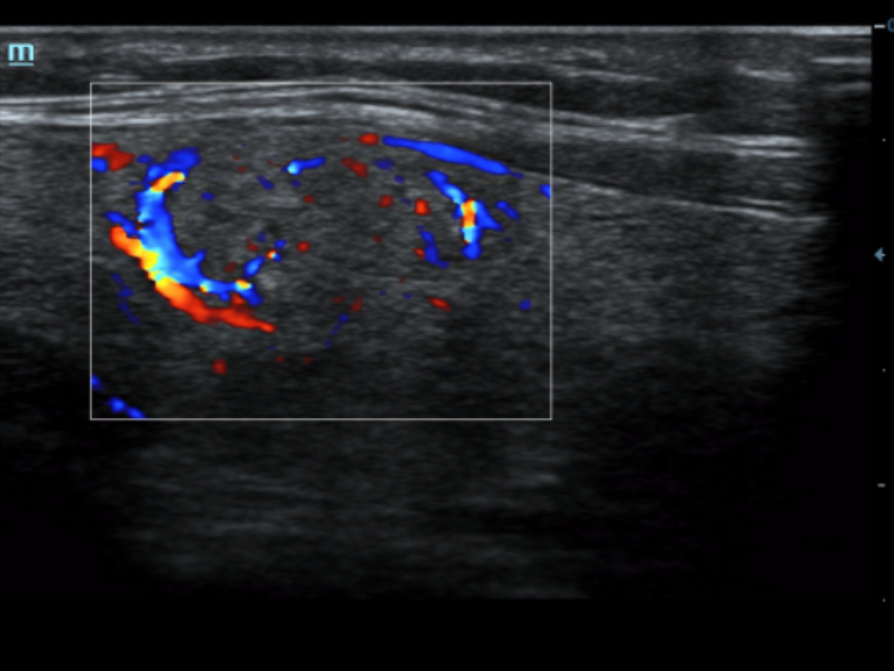

iBeam? (obrazowanie krzy?owe)

HR Flow?